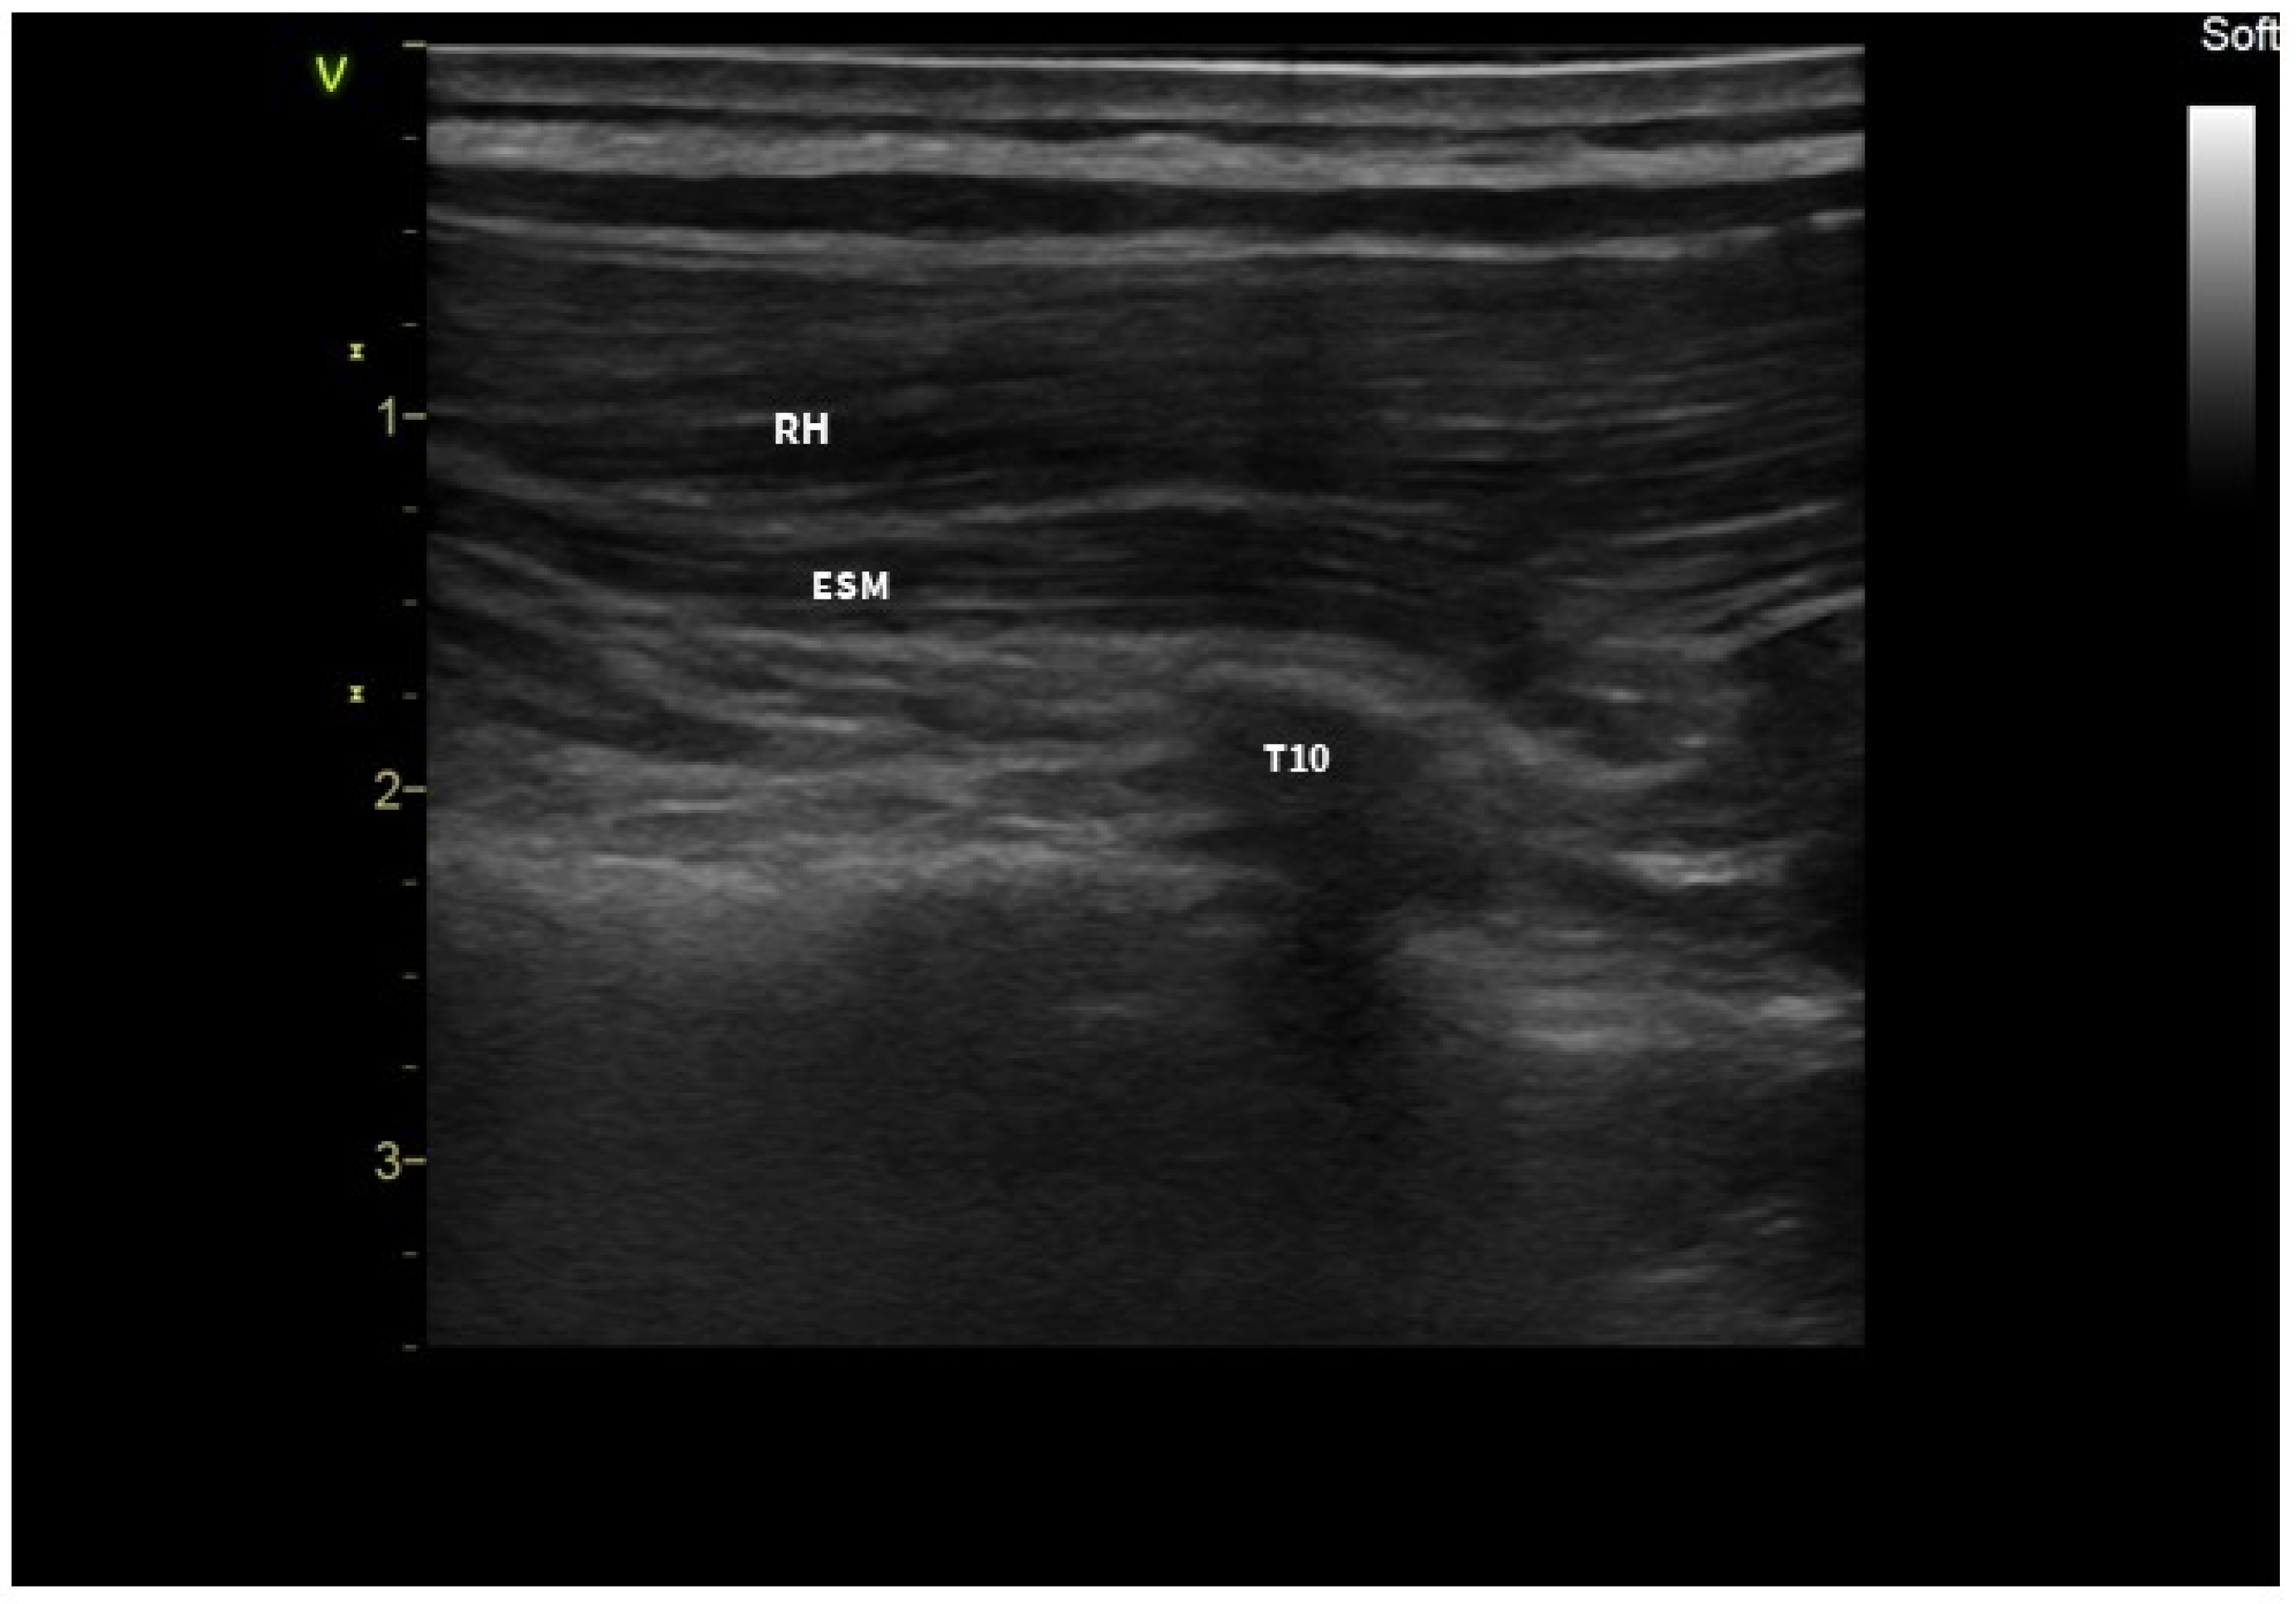

2. Case Presentation